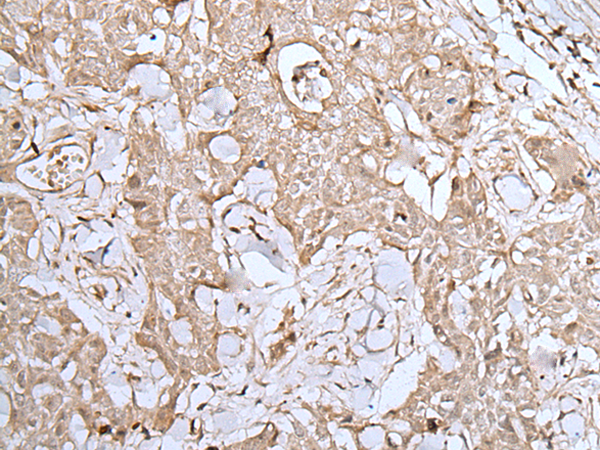

The image is immunohistochemistry of paraffin-embedded Human lung cancer tissue using P12727(DUSP3 Antibody) at dilution 1/25. (Original magnification: ×200) |